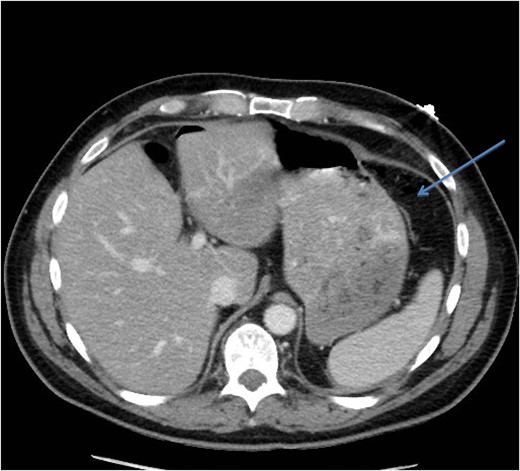

A CT scan demonstrated significant soft tissue stranding/edema of the omentum in the left hemi-abdomen. In addition, there was mild ascites and multiple scattered locules of air (Figs 3–5). No other abnormality of the small or large bowel was identified. He was admitted for observation and broad-spectrum antibiotic therapy was initiated. On post admission day 2, he became diffusely peritonitic, febrile with a temperature of 39.1°C and his oxygen requirements increased to 12 l/min.

CT scan (axial image) demonstrating gas within the omentum (arrow).